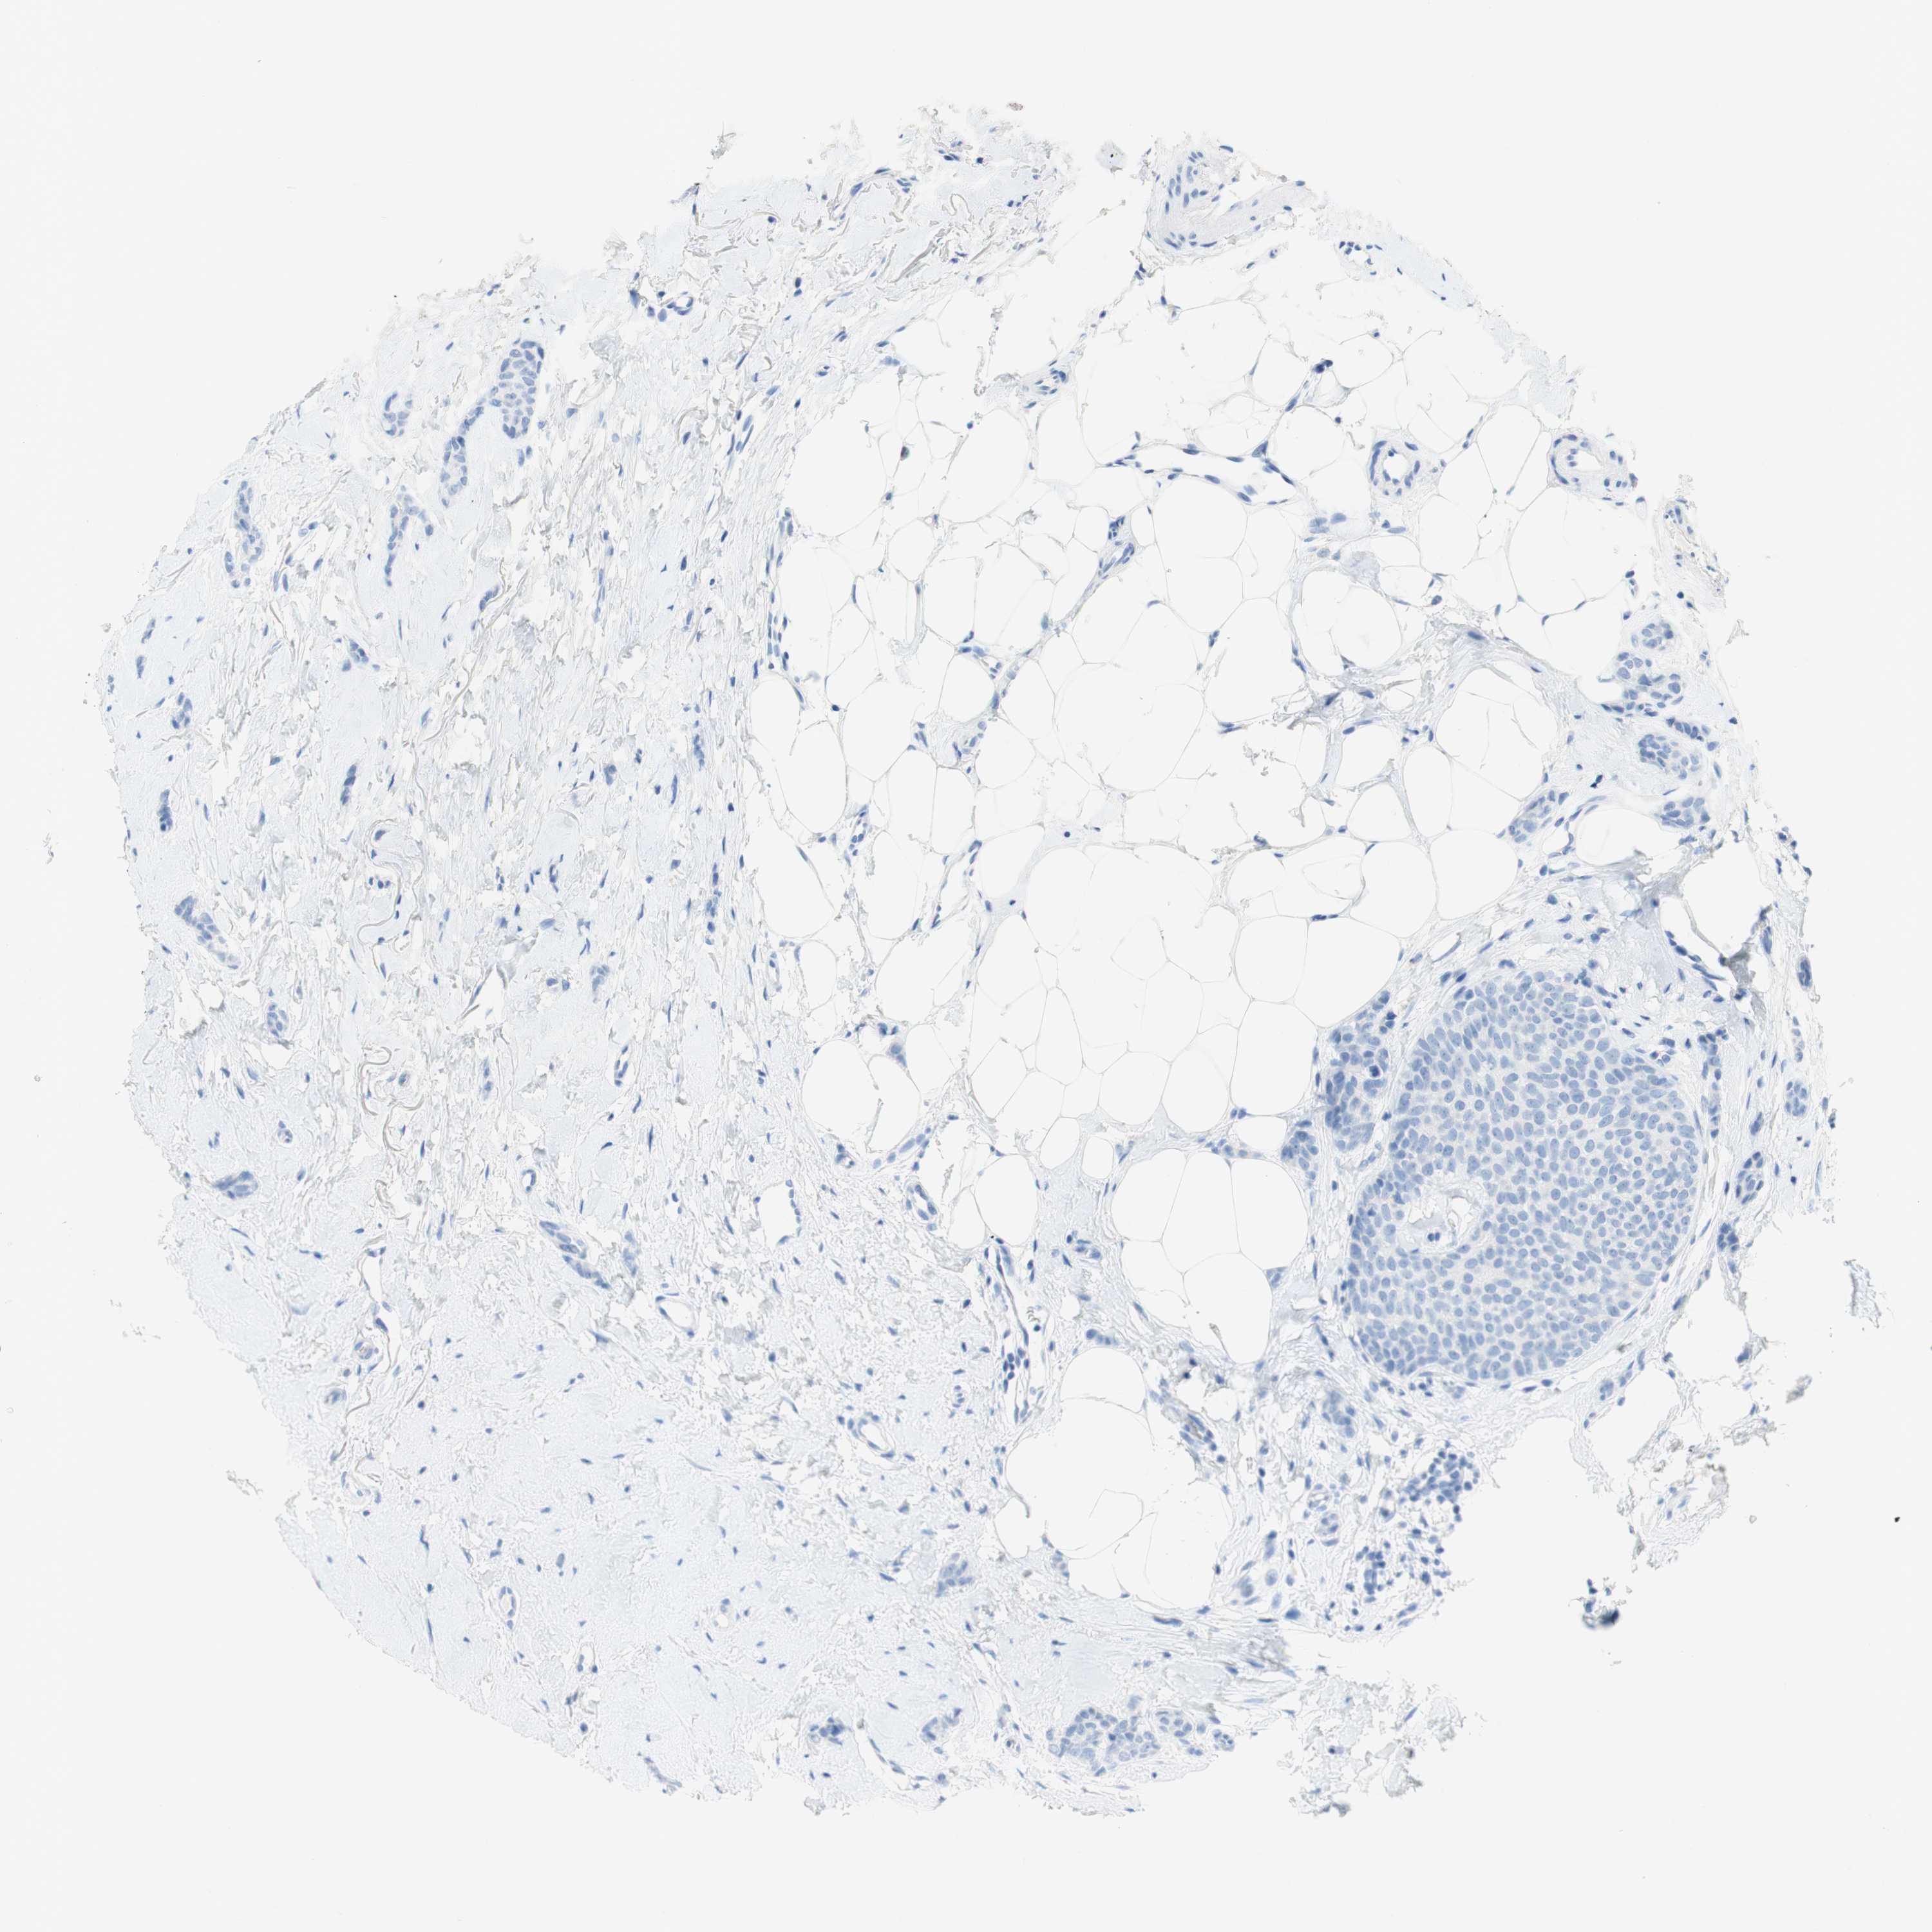

CANCER BREAST CANCER Show tissue menu

BRCA TCGA BRCA VALIDATION PROTEIN EXPRESSION